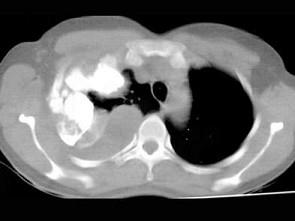

问题 男,66岁,剧烈胸痛,请结合CT图像,选择最可能的诊断 ( )

选项 A、右侧肺不张 B、右侧肺肺癌 C、右肺癌侵犯胸膜 D、右侧胸膜间皮瘤 E、右侧胸腔积液胸膜钙化

答案 D